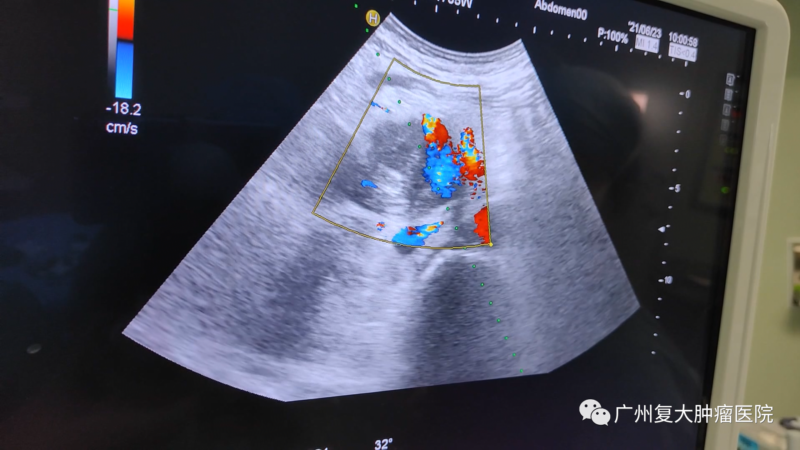

針對(duì)劉叔的病情,我院牛立志院長(zhǎng)為他實(shí)行胰腺及肝臟轉(zhuǎn)移瘤穿刺活檢+胰腺及肝臟轉(zhuǎn)移瘤納米刀消融術(shù)。在超聲+CT引導(dǎo)下,全程監(jiān)測(cè)、設(shè)計(jì)布針路線(xiàn)、避開(kāi)重要的血管,將“納米刀”精準(zhǔn)植入腫瘤,以達(dá)到減輕腫瘤負(fù)荷,減緩疾病進(jìn)展的效果。

納米刀消融過(guò)程

影像(如超聲、CT等)引導(dǎo)下經(jīng)皮納米刀消融,無(wú)需開(kāi)腹,只需幾個(gè)針尖大小的小孔,達(dá)到殺滅腫瘤的效果,減輕病人痛苦。在影像設(shè)備的輔助下,可以對(duì)納米刀探針的定位、標(biāo)靶區(qū)域的消融過(guò)程以及最終消融區(qū)的大小進(jìn)行實(shí)時(shí)監(jiān)控,且影像中消融區(qū)邊界的精確度可與組織學(xué)上的精確度相媲美。另外,實(shí)時(shí)監(jiān)測(cè)還可以讓醫(yī)生觀(guān)察到消融區(qū)周?chē)M織的變化,從而推斷出并發(fā)癥出現(xiàn)的可能性,保障病人的安全以及有助于其術(shù)后快速恢復(fù)。

影像設(shè)備實(shí)時(shí)監(jiān)控